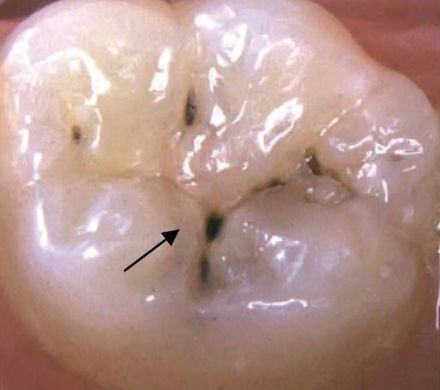

别看很多蛀牙表面只是一个小黑点,其实要比你想象中的严重得多,里面可能已经坏了这么大哦!

再矿化的牙釉质跟正常的牙釉质一样,起着抵御外来酸的作用。但如果你的蛀牙已经形成,再矿化的牙釉质也会阻止唾液进一步深入到脱矿的深层牙釉质或牙本质里面。反而起到了保护蛀牙的作用,让致龋菌在牙齿里面肆意繁殖。这就是为什么我们有时看到的蛀牙是隐隐约约看到下方有点暗色,晕染过的墨渍一样。

上图就是表面再矿化的牙釉质,里面的蛀牙还在继续龋坏。